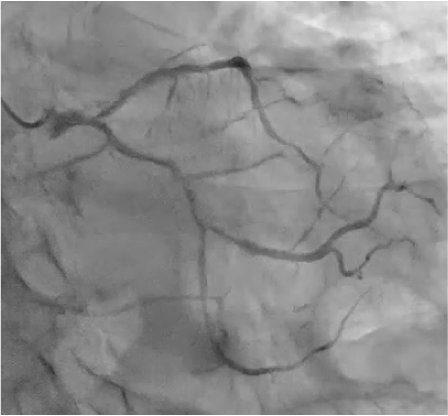

LCA CAG

RCA CAG